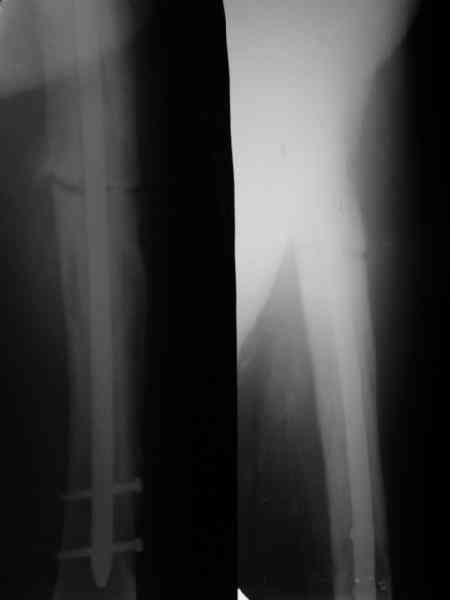

При переломах на фоне болезни Педжета металлоконструкция часто служит эндопротезом, несущим нагрузку. Динамизация индивидуальна,- по рентген-динамике. Основной упор- на медикаментозную терапию- см. канд. дисс. Колондаева А.Ф.

Стержень можно было бы поставить подлиннее.

Анатолий Леонидович Баранецкий совершенно прав. Сращения ждать надо очень долго (несколько лет). Главное - гвоздь попрочнее и потолще. Раньше использовали мощный 4-гранный штифт ЦИТО. Можно и гвоздь с блокированием (блокировать только с одной стороны) - но ни в коем случае не полый. И ходить с тростью. Сейчас в России зарегистрирован очень хороший препарат (с декабря 2006 г.) - Акласта, по 100 мл - обычно хватает 1 (реже двух) инфузии для полной ремиссии (в Белоруссии он появился даже раньше, чем на Украине и в Россиии). Немного хуже Аредия, ее надо в сумме 180-240 мг, полная эффективность 84%. Все в\в кап. бисфосфонаты вызывают выраженную гипокальциемию. Поэтому приходится назначать по нескольку лет альфакальцидол под контролем Са крови (каждые 3-6 мес). Сперва по 6-8 капсул (капель), т.е 1,5-2,0 мкг, затем через 2-4 месяца - по 0,5-0,75 мкг. Препараты Са по 1-2 гр. в день, очень долго.